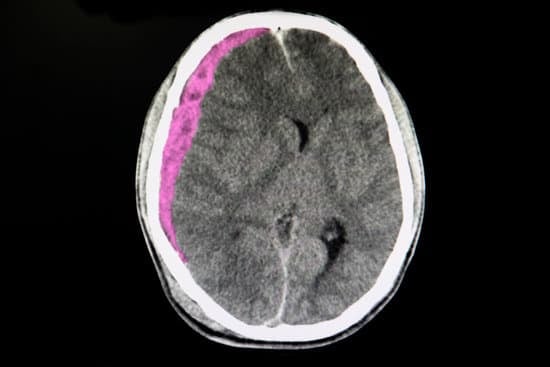

외상외과 수술은 다양한 외상성 부상을 치료하는 외과 분야로, 골절, 내장 손상, 두부 외상 등 중증 외상 환자를 대상으로 합니다.

외상외과 의사는 골절 고정, 출혈 제어, 장기 복구 및 신경 손상 복원 등의 작업을 수행하며, 수술은 대개 응급 상황에서 이루어집니다.